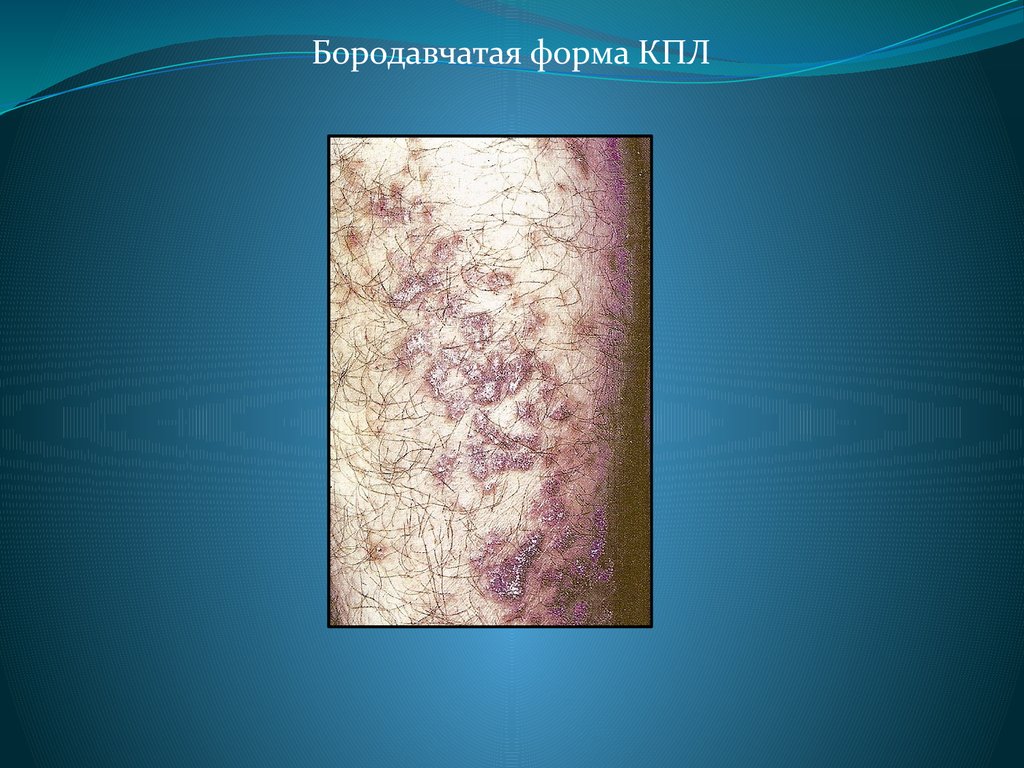

Фото Красного Плоского

Фото Красного Плоского 103 фото